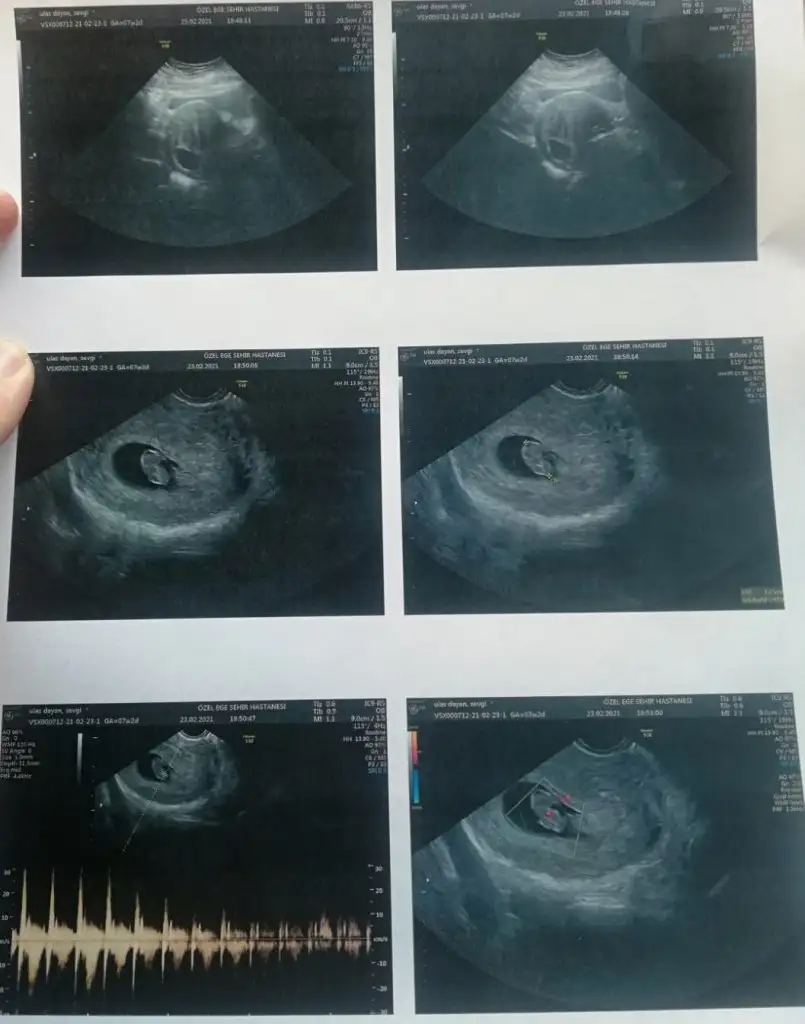

Cinsiyet için teoriler bakımından benim bıdığa da bir tahmin yapsanız çok sevinirim. 11+4 ama ölçümde 1 haftaya yakın ilerde görünüyor.

Eklentiler

• IMG_20210224_105405.webp

IMG_20210224_105405.webp

15,6 KB · Görüntüleme: 79

Alnı çıkık olmasa erkek gibi kafa yapısı. Nub'u belli olmuyor ona daha garanti diyorlar